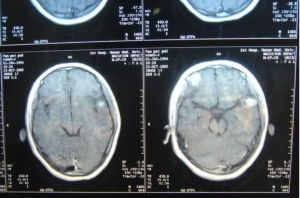

膠質瘤的診斷,根據其生物學特徵、年齡、性別、好發部位及臨床過程進行分析,在病史及體徵基礎上,採用電生理、超音波、放射性核素、放射學及核磁共振等輔助檢查,定位正確率幾乎是100%,定性診斷正確率可在90%以上。腦膠質瘤由於腫瘤呈浸潤性生長,與腦組織無明確分界,難以徹底切除,手術治療的原則是在保存神經功能的前提下儘可能切除腫瘤。早期腫瘤較小又位於適當部位者可爭取全部切除。位於額葉的腫瘤,可作腦葉切除。當額葉或顳葉腫瘤範圍較廣不能全部切除時,可同時切除額極或顳極作內減壓術。腫瘤位於運動、言語區而無明顯偏癱、失語者,宜注意保存神經功能,適當切除腫瘤,避免發生嚴重後遺症。腦室腫瘤宜從非功能區切開腦組織進入腦室,儘可能切除腫瘤,解除腦梗阻。位於丘腦、腦幹的膠質瘤,除小的結節性或囊性者可作切除外,一般作分流術,緩解增高的顱內壓後,進行中醫藥綜合治療。